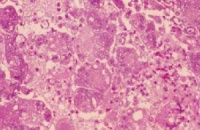

喉痛、声嘶、喉喘鸣和呼吸困难,并可伴发热恶寒,咽喉疼痛,喉镜下可见粘膜呈深红色水肿、表面发亮,喘鸣,声嘶,呼吸困难,甚则窒息,喉镜下可见喉粘膜弥漫性水肿,苍白。